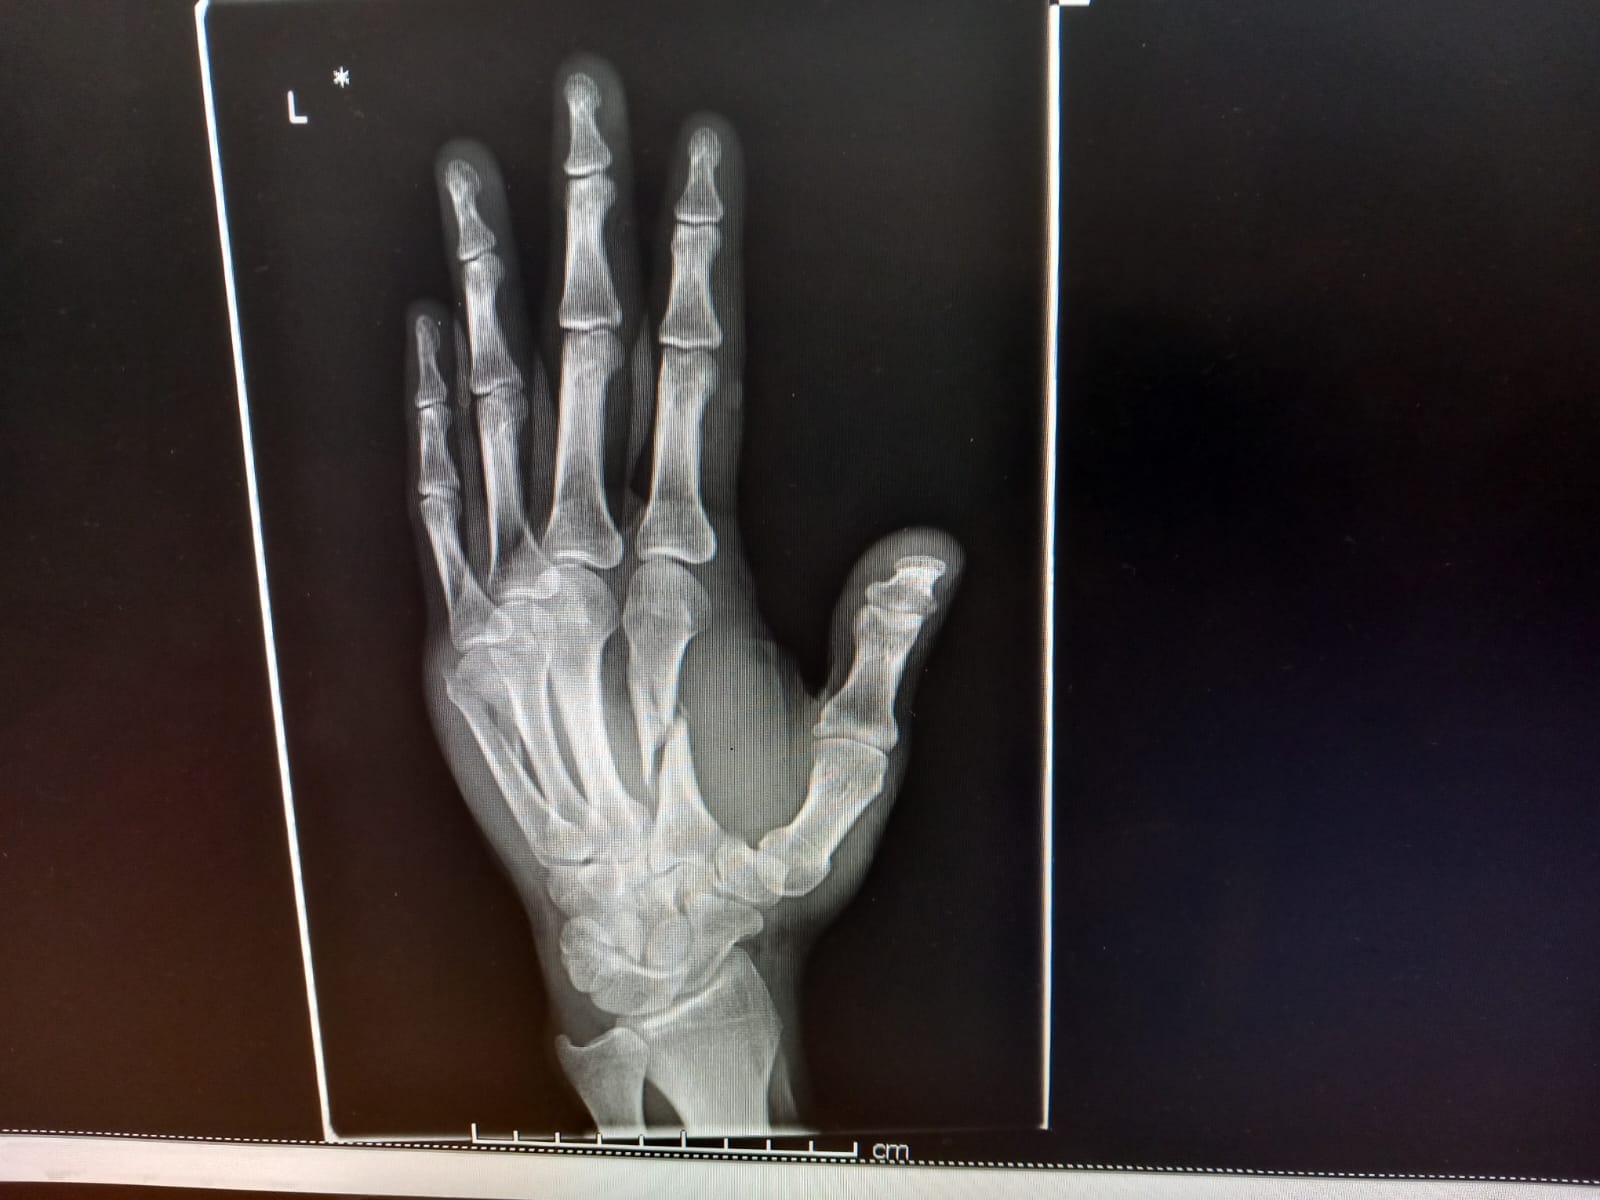

Not Stoked.